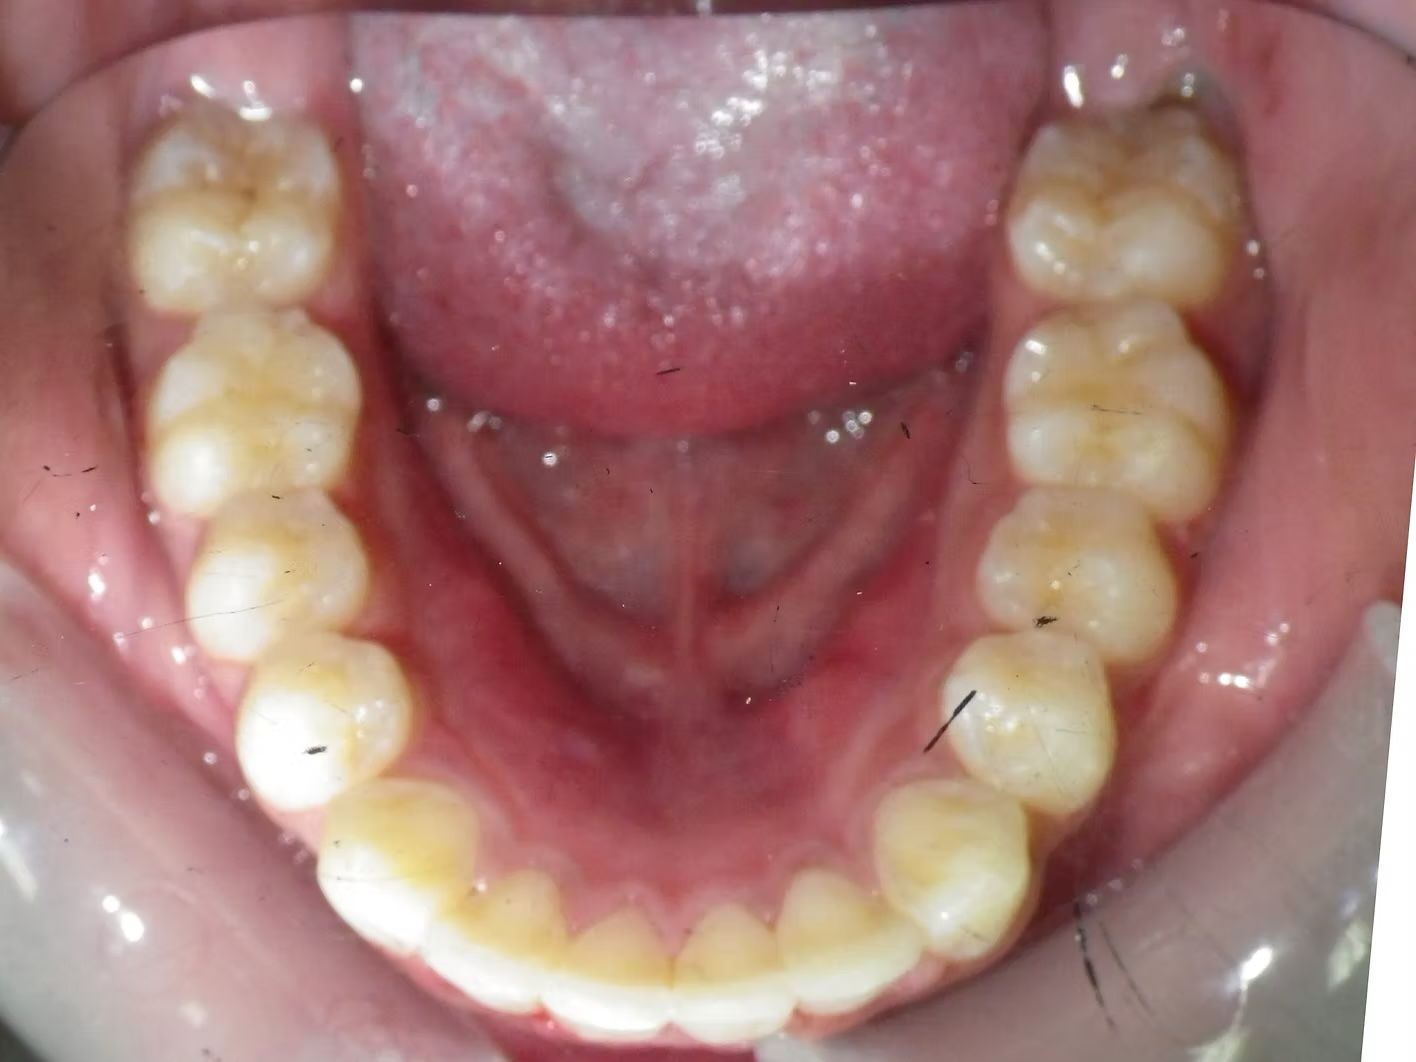

Imset

Imset came to see Dr. Bret because he felt like the upper and lower teeth were too crowded. The lower canines were in cross-bite with the upper teeth and there was significant crowding in the lower arch. He previously had 2 teeth pulled in the top and at the time none in the bottom. This made the top jaw smaller than the lower and the lower teeth didn't have room to fit inside the top teeth. We had 2 lower teeth extracted, and then aligned the upper and lower teeth to fit excellently together- no more crowding!